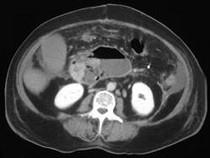

问题 女,33岁,发热,中上腹压痛反跳痛,血清淀粉酶增高,CT检查如图,最可能的诊断是 ( )

选项 A.急性胰腺炎 B.慢性胰腺炎 C.胰腺脓肿 D.胰腺假性囊肿 E.胰腺癌

答案 C